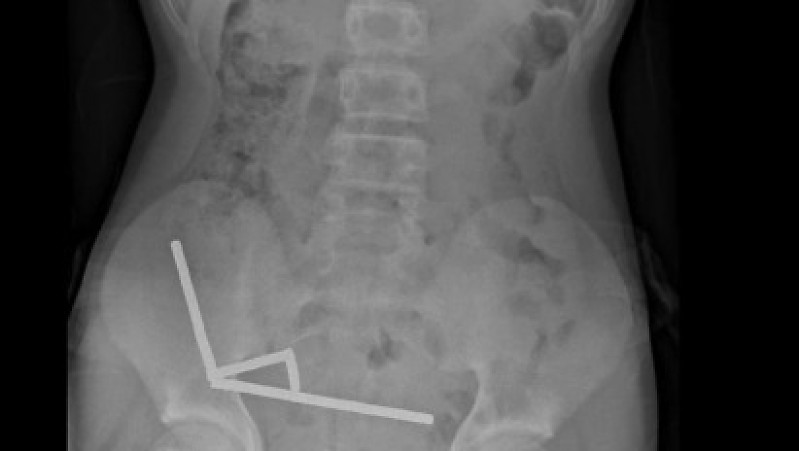

Exames revelaram que os ímãs haviam se agrupado em quatro correntes na parte inferior direita do abdômen, unindo diferentes seções do intestino com sua força magnética, segundo o relatório, que observou que algumas imagens foram distorcidas pelos ímãs. Os médicos então procederam com uma cirurgia exploratória.

Durante o procedimento, os cirurgiões descobriram que as correntes de ímãs estavam causando necrose por pressão – morte do tecido por pressão prolongada – em partes do intestino delgado e grosso. Eles conseguiram remover os ímãs, mas o menino precisou ter parte do intestino removido. Ele passou oito dias se recuperando no hospital antes de receber alta, informou o relatório.